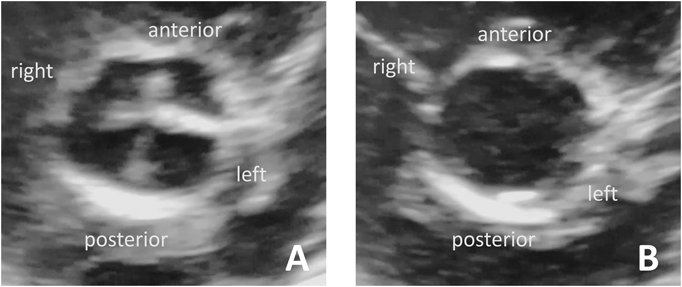

A girl weighing 2,988 g was born without asphyxia at a gestational age of 38 weeks by scheduled cesarean section as her mother previously underwent cesarean section. Her mother was administered levothyroxine for well-controlled hypothyroidism; however, her father and two siblings were healthy. After birth, the patient developed tachypnea with mild hypoxia. No cardiac murmur was noted on auscultation. Although the ductus arteriosus demonstrated physiological patency on echocardiography, no other critical heart anomalies were identified. A diagnosis of transient tachypnea of the newborn was established using chest X-ray. The patient was then admitted to the neonatal intensive care unit of our institute and was administered low-concentration oxygen. Her respiratory impairment rapidly improved, and oxygen administration was discontinued at the age of 1 day. Thereafter, her condition was uneventful, except for the ongoing phototherapy for hyperbilirubinemia. Although echocardiography revealed a completely closed ductus arteriosus at the age of 6 days, a quadricuspid aortic valve (QAV) was incidentally detected (Fig. 1A, B). It was difficult to accurately determine the type of QAV using transthoracic echocardiography alone because the cusps of the aortic valve seemed to differ only slightly in size, and there were no extremely small cusps. QAV of type A, C, or E based on the Hurwitz and Roberts classification was considered to be most likely. The thickened coaptation line between the left anterior and left posterior leaflets was noticeable during diastole (Fig. 1A). Furthermore, the mobility of the commissure seemed to be slightly restricted in systole (movie), suggesting some deformities of the leaflets and commissure. However, color and pulse Doppler echocardiography showed neither valvular regurgitation (AR) nor a stenotic flow pattern, such as turbulent flow. Unfortunately, the coronary anomalies were not evaluated in detail because we did not focus on them. The patient grew well until the age of 1 month, when she was referred to another institute for her regular heart checkup, which revealed a systolic heart murmur. Echocardiography revealed mild pulmonary stenosis with a tricuspid pulmonary valve.

(A) At the diastole: four cusps differing only slightly in size are noted. The coaptation line between the left anterior and the left posterior leaflets is thickened. (B) At the systole.